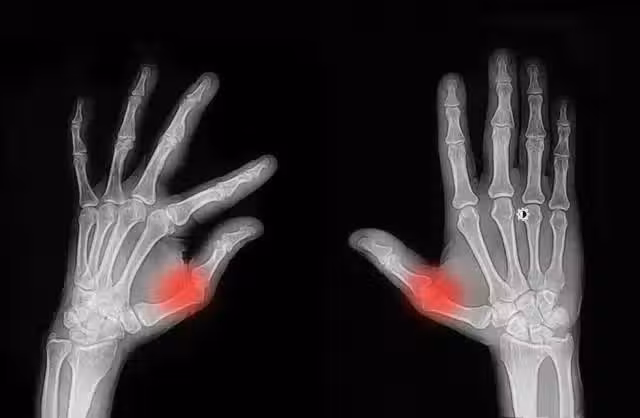

經常掰手指,老了會得關節炎?這樣響沒事,又響又痛可能是這些病

1. 適度運動為了保持手指關節的靈活性和健康狀態,我們可以進行適度的手指運動。例如,輕輕轉動手指關節、進行手指操等。這些運動可以促進關節內的血液循環和軟組織代謝,有助於保持關節的健康狀態